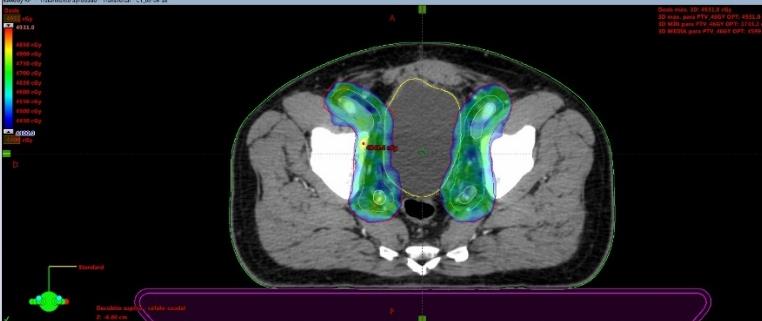

Se presentan figuras de un caso clínico de nuestro centro. Paciente de 57 años, APE: 6.5, Biopsia Gleason 7 (3+4) 2/6 sextantes. Etapificación (-), Rechaza cirugía.